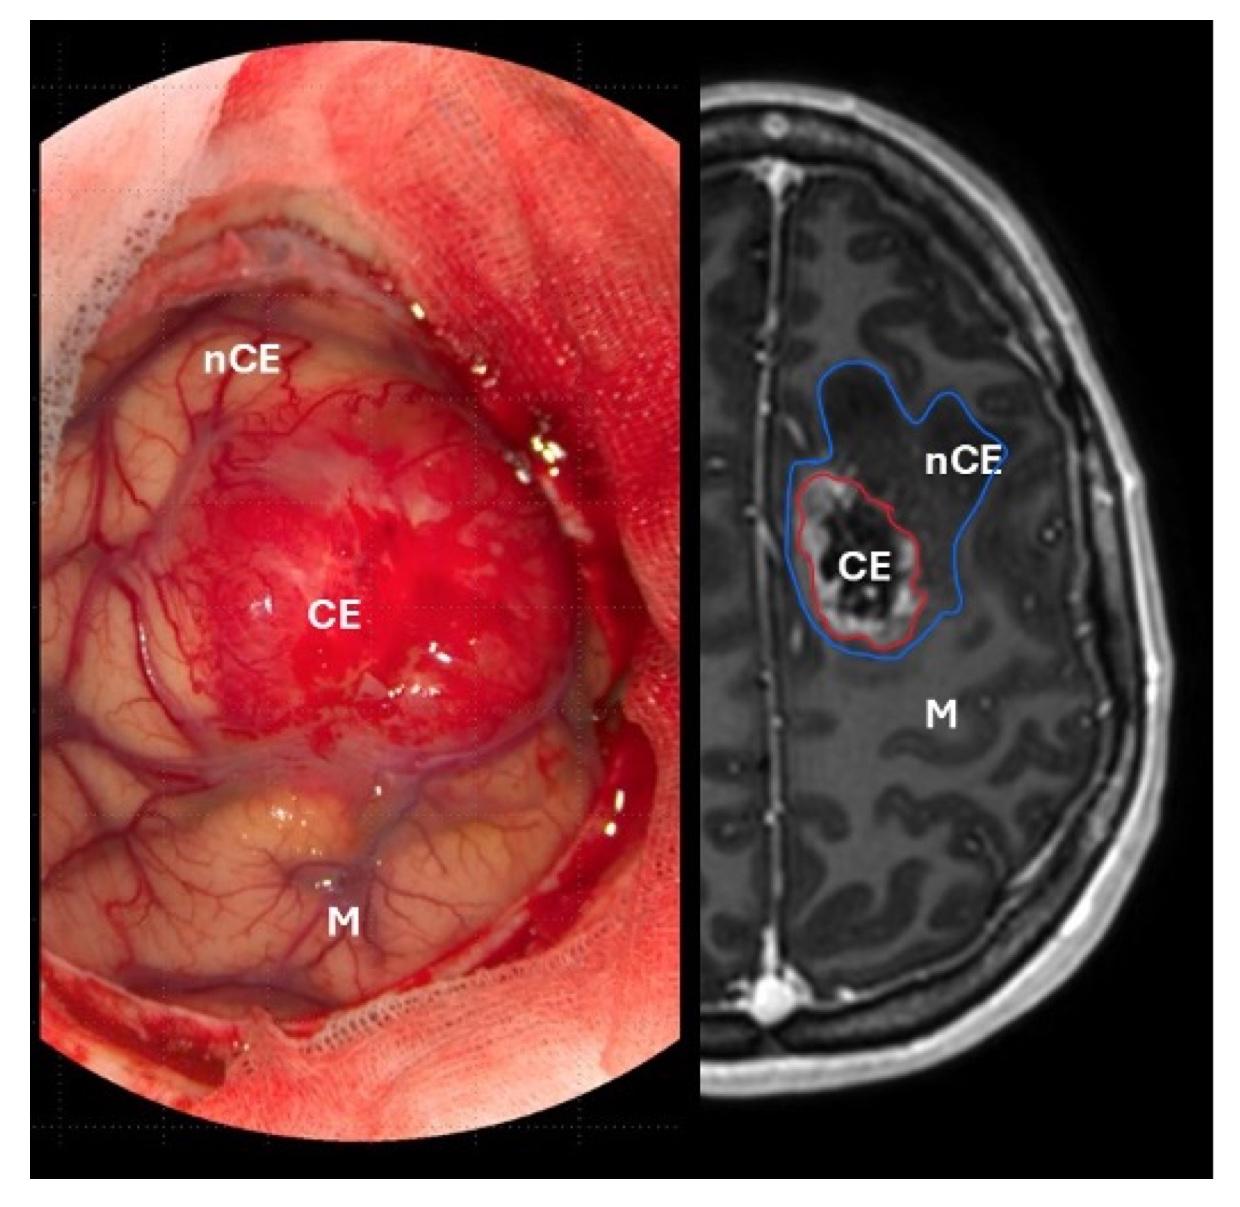

1. Til venstre: peroperativt bilde av malign og ekspansiv tumor med rik neovaskularisering. Til høyre: utdrag av MR (T1-serie med kontrast), som viser omfanget av tumor i hjernen. Kontrastladende del av tumor (CE) har vært det etablerte målet for reseksjon, men er nylig blitt erstattet med et mål om supramaksimal reseksjon som også omfatter ikke-kontrastladende tumor (nCE). Området for motorisk kontroll av høyre hånd er også markert (M).

Kirurgi er den første og viktigste behandlingsmodaliteten ved glioblastom. Det sikrer vev for histopatologisk og molekylær diagnose, lindrer symptomer, reduserer tumorbyrden og bidrar til lengre overlevelse. Målet er maksimal trygg reseksjon – å fjerne mest mulig tumorvev uten å påføre pasienten varig nevrologisk skade. En rekke studier har vist en klar sammenheng mellom grad av reseksjon og overlevelse (8,9,10), noe som også er vist i norske populasjonsdata (6). Data fra det norske kvalitetsregisteret fra 2019-2023 viser at 85 % av pasientene gjennomgikk reseksjon som primærbehandling, mens 15 % gjennomgikk en diagnostisk biopsi (11). Den postoperative 30-dagers mortaliteten var 1,5 % etter reseksjon (12).

Den moderne forståelsen av reseksjonsgrad er standardisert gjennom klassifikasjonen utarbeidet av RANO-resect (Response Assessment in Neuro-Oncology) (13). Klassifikasjonen baseres på postoperativ MR utført innen 72 timer etter kirurgi, og deler reseksjonen i fire klasser avhengig av gjenværende tumorbyrde:

• Klasse 1: Supramaksimal reseksjon – ingen kontrastladende resttumor + ≤5 cm³ ikke-kontrastladende tumor.

• Klasse 2: Maksimal reseksjon – ≤1 cm³ kontrastladende resttumor

• Klasse 3: Subtotal reseksjon – >1 cm³ kontrastladende resttumor

• Klasse 4: Diagnostisk biopsi

Klassifikasjonen er basert på retrospektive, multisenterdata fra 1008 pasienter med nydiagnostisert glioblastom. Pasienter der man oppnådde en klasse 1-reseksjon hadde en median overlevelse på 24 måneder sammenlignet med 19, 15 og 10 måneder i henholdsvis klasse 2-4 (Figur 2). Selv om en mer omfattende reseksjon er assosiert med lengre overlevelse, må inngrepet utføres med varsomhet. Nye, alvorlige nevrologiske utfall etter kirurgi medfører et betydelig prognosetap (4). Det er derfor avgjørende å balansere graden av reseksjon mot risikoen for varig nevrologisk skade, og å unngå alvorlige, permanente funksjonsutfall.